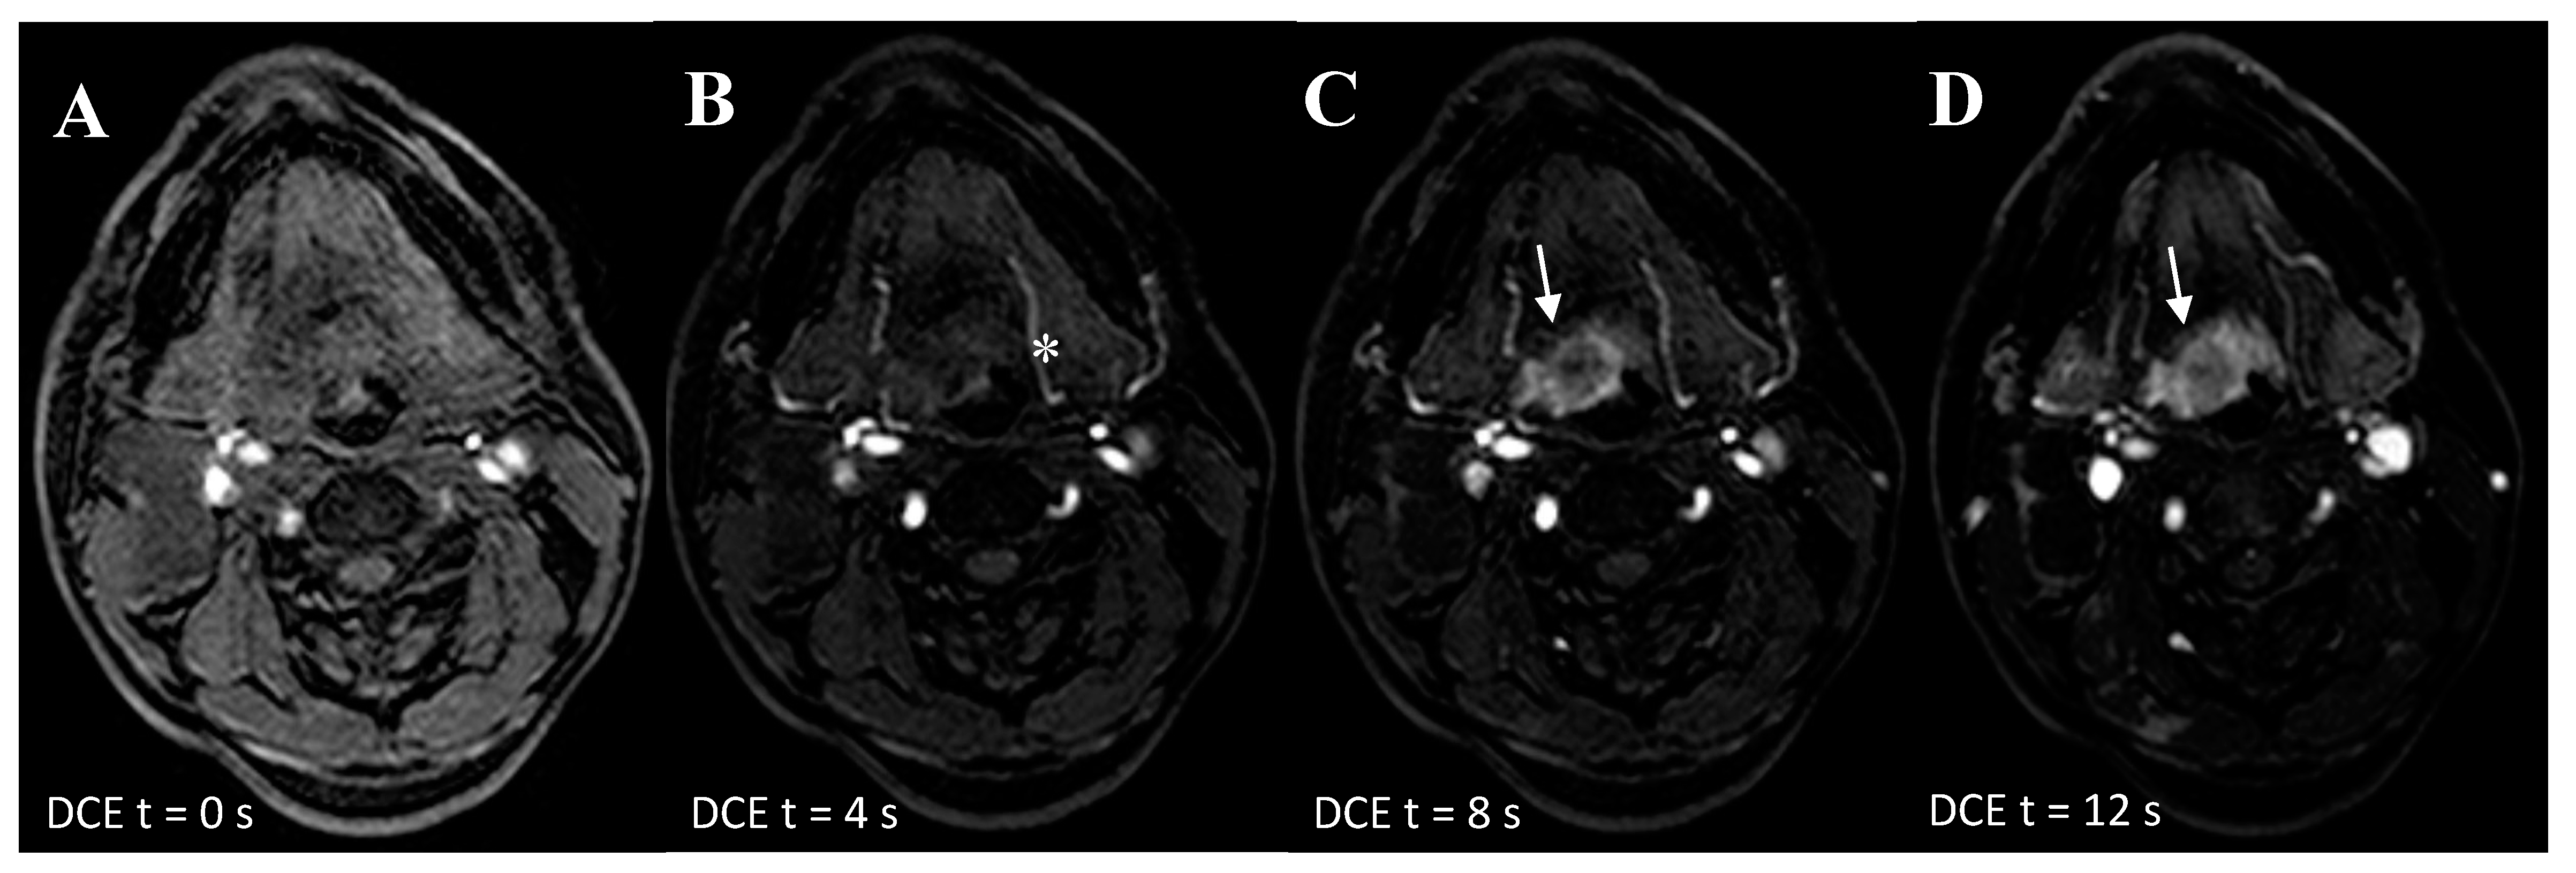

Figure 2.

Ultra-fast DCE in a 53-year-old patient with an overt primary tumor in the tongue base. (A) At T = 0 seconds is the first frame in which the contrast enters the carotid and vertebral arteries. (B) At T = 4 seconds later, the contrast flows in the arterial branches of the external carotids (*). (C) At T = 8 seconds the contrast agent has ‘washed-in’ the hypervascular malignant lesion at the base of tongue (arrow). (D) At T =12 seconds, the contrast agent is still in the hypervascular lesion. At this stage, the surrounding oropharyngeal mucosa show also contrast enhancement (Δ).

The additional value of ultrafast-DCE over DWI and 18F-FDG-PET/CT is that it might capture complementary unique tumor characteristics. Although the precise physiological explanation of enhancement on DCE remains ambiguous (e.g., angiogenesis and increased microvessel density) [19], early intensity changes were indicative for malignancy (Figure 2). This is in line with studies in breast cancer with an earlier time of arrival of contrast bolus in the malignant lesion [15,16,17]. Although the thin mucosal hypervascular layer and normal tonsillar tissue might interfere with the detection UPT, no other hypervascular lesions are generally present in the head and neck area. This could provide additional value for UPT detection by adding detection based on lesion vascularity, to DWI as a sign of tissue cellular density and 18F-FDG-PET/CT as a sign of tumor metabolism. Due to the limited spatial resolution of 18F-FDG-PET/CT for detecting small primary lesions, the addition of ultrafast-DCE may provide more confidence for the radiologist to mark a suspicious lesion as being malignant or benign (Figure 1, Figures S2 and S3) or when DWI and 18F-FDG-PET/CT are inconclusive. Furthermore, a similar high, positive agreement was found for ultrafast-DCE (77.6%) compared to DWI (76.6%) and 18F-FDG-PET/CT (71%), although more experience is gained with DWI and 18F-FDG-PET/CT. Also, the addition of ultrafast-DCE might enhance demarcation of tumoral boundaries, in order to optimize radiotherapy.